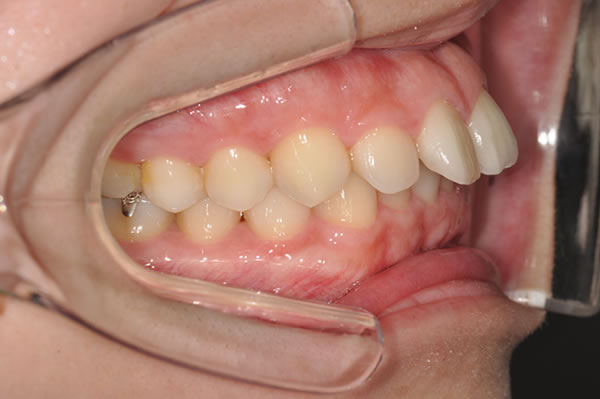

上顎前突症の治療例

上顎前突症(出っ歯)の矯正症例 ケース01

上顎前突症(出っ歯)の矯正症例 ケース02